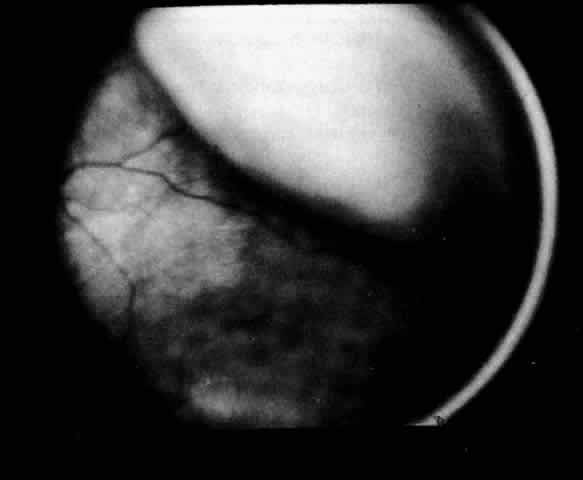

A ciliochoroidal effusion and other benign processes may be accurately differentiated from choroidal tumors with B-scan ultrasonography, as reported by Coleman29 in more than 60% of cases. Ultrasonography can distinguish a ciliochoroidal effusion from a retinal detachment by the acute anterior angle of the acoustic shadow of an effusion and its extension anterior to the ora serrata (Fig. 6). The ultrasonic finding of a diffusely thickened choroid posteriorly should alert the ultrasonographer and ophthalmologist to the possibility of a ciliochoroidal detachment more anteriorly. If posterior choroidal thickening is not associated with a peripheral ciliochoroidal detachment, other clinical entities should be excluded, such as posterior scleritis, choroidal inflammation, and intraocular tumors.30 Scleral infolding may ophthalmoscopically simulate a ciliochoroidal effusion in a hypotonous eye, and B-scan ultrasonography may assist in the diagnosis.31

Fig. 6. B-scan ultrasound of a choroidal effusion. An acute anterior angle and extension anterior to the ora serrata help to distinguish this as a choroidal effusion, rather than a retinal detachment.